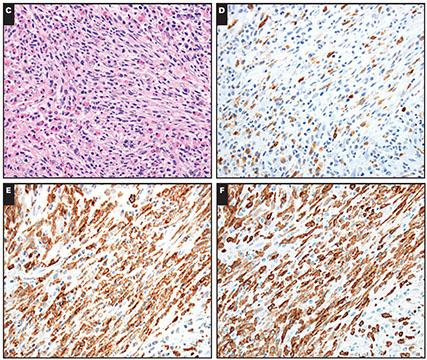

Micro:

DRESS mimicking LCH. Case 229 also showed expansion/effacement of the paracortex (D, ×10) by cells with grooved nuclei consistent with Langerhans cells (E, ×40) confirmed by CD1a immunohistochemistry (F, ×10). [4]

Reactive lymphadenopathies in drug reaction with eosinophilia and systemic symptoms. A-C, Case 262 showed paracortical expansion of lymphocytes and histiocytes (A, ×20), with CD3 showing a predominance of T cells (B, ×20) and CD30 highlighting increased immunoblasts (C, ×20).